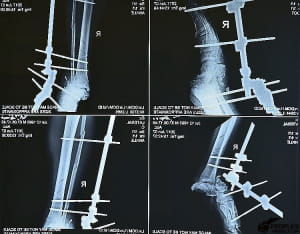

Лікар ортопед-травматолог Володимир Оксимець пояснює: "Петі дуже пощастило. Те, що він не повністю настав на кінцівку, він був на навприсядки. І у нього було хороше взуття… Подивившись перший раз, я розумію, що воно живе і можна боротися за ногу". За спиною лікаря – знімки правої ноги Петра, на яких немає п'яти. Її доведеться відростити, як це зробили, наприклад, іншому пацієнту.

Нову кістку створять з клітин пацієнта. Їх уже взяли і процес росту розпочався. Це інноваційна технологія, яка допомогла вже більш як 40 військовослужбовцям. Проект "Біотех-реабілітація" втілюють волонтери "People's Project".